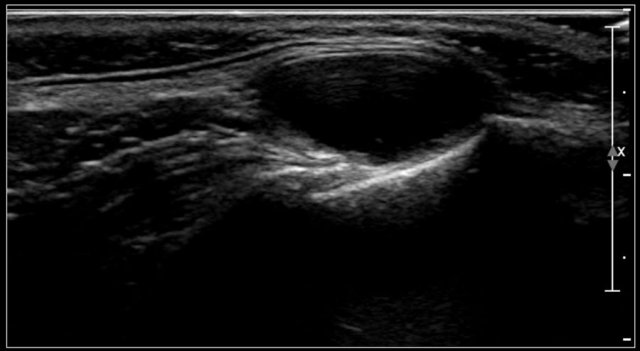

Branchial cleft cyst

Most branchial cysts are remnants of the second brancial cleft.

Cysts at the level of the thyroid gland can be remnants of the third or fourth branchial cleft.

Incomplete obliteration results in either a cyst (75%), a sinus or a fistula (25%).

Cysts present as painless masses, sometimes appearing suddenly after internal hemorrhage.

They are located along the anterior border of the sternocleidomastoid muscle, lateral to the common carotid artery, and if more cranially between the internal and external carotid artery.

Sometimes a beak sign may be seen as a curved rim of the lesion pointing medially between the internal and external carotid.

On ultrasound they often contains internal echoes caused by debris, which consists of cholesterol crystals.

The cyst is usually compressible, which results in movement of the content.

This may not be the case in a cyst with a fresh internal hemorrhage.

They can inflame and present with an empyema.

Here another branchial cyst with a typical location superficial to the carotid artery bifurcation.